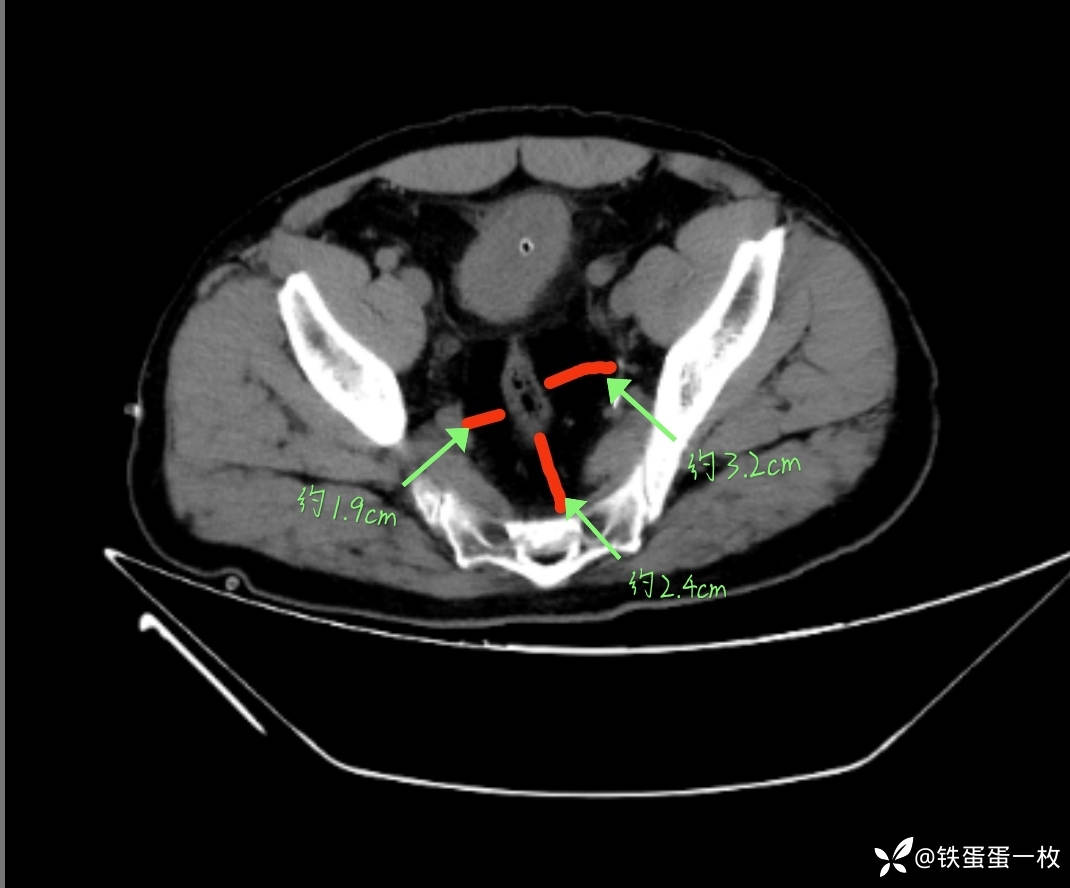

1)CT检查可以发现PL患者多出现较为明显的肾积水,膀胱位置也发生改变;

盆腔内均匀低密度影,平均C值-90HU,存在大量脂肪,但无包膜,与膀胱四周正常脂肪组织间界限不清。

膀胱位置改变、膀胱壁增厚